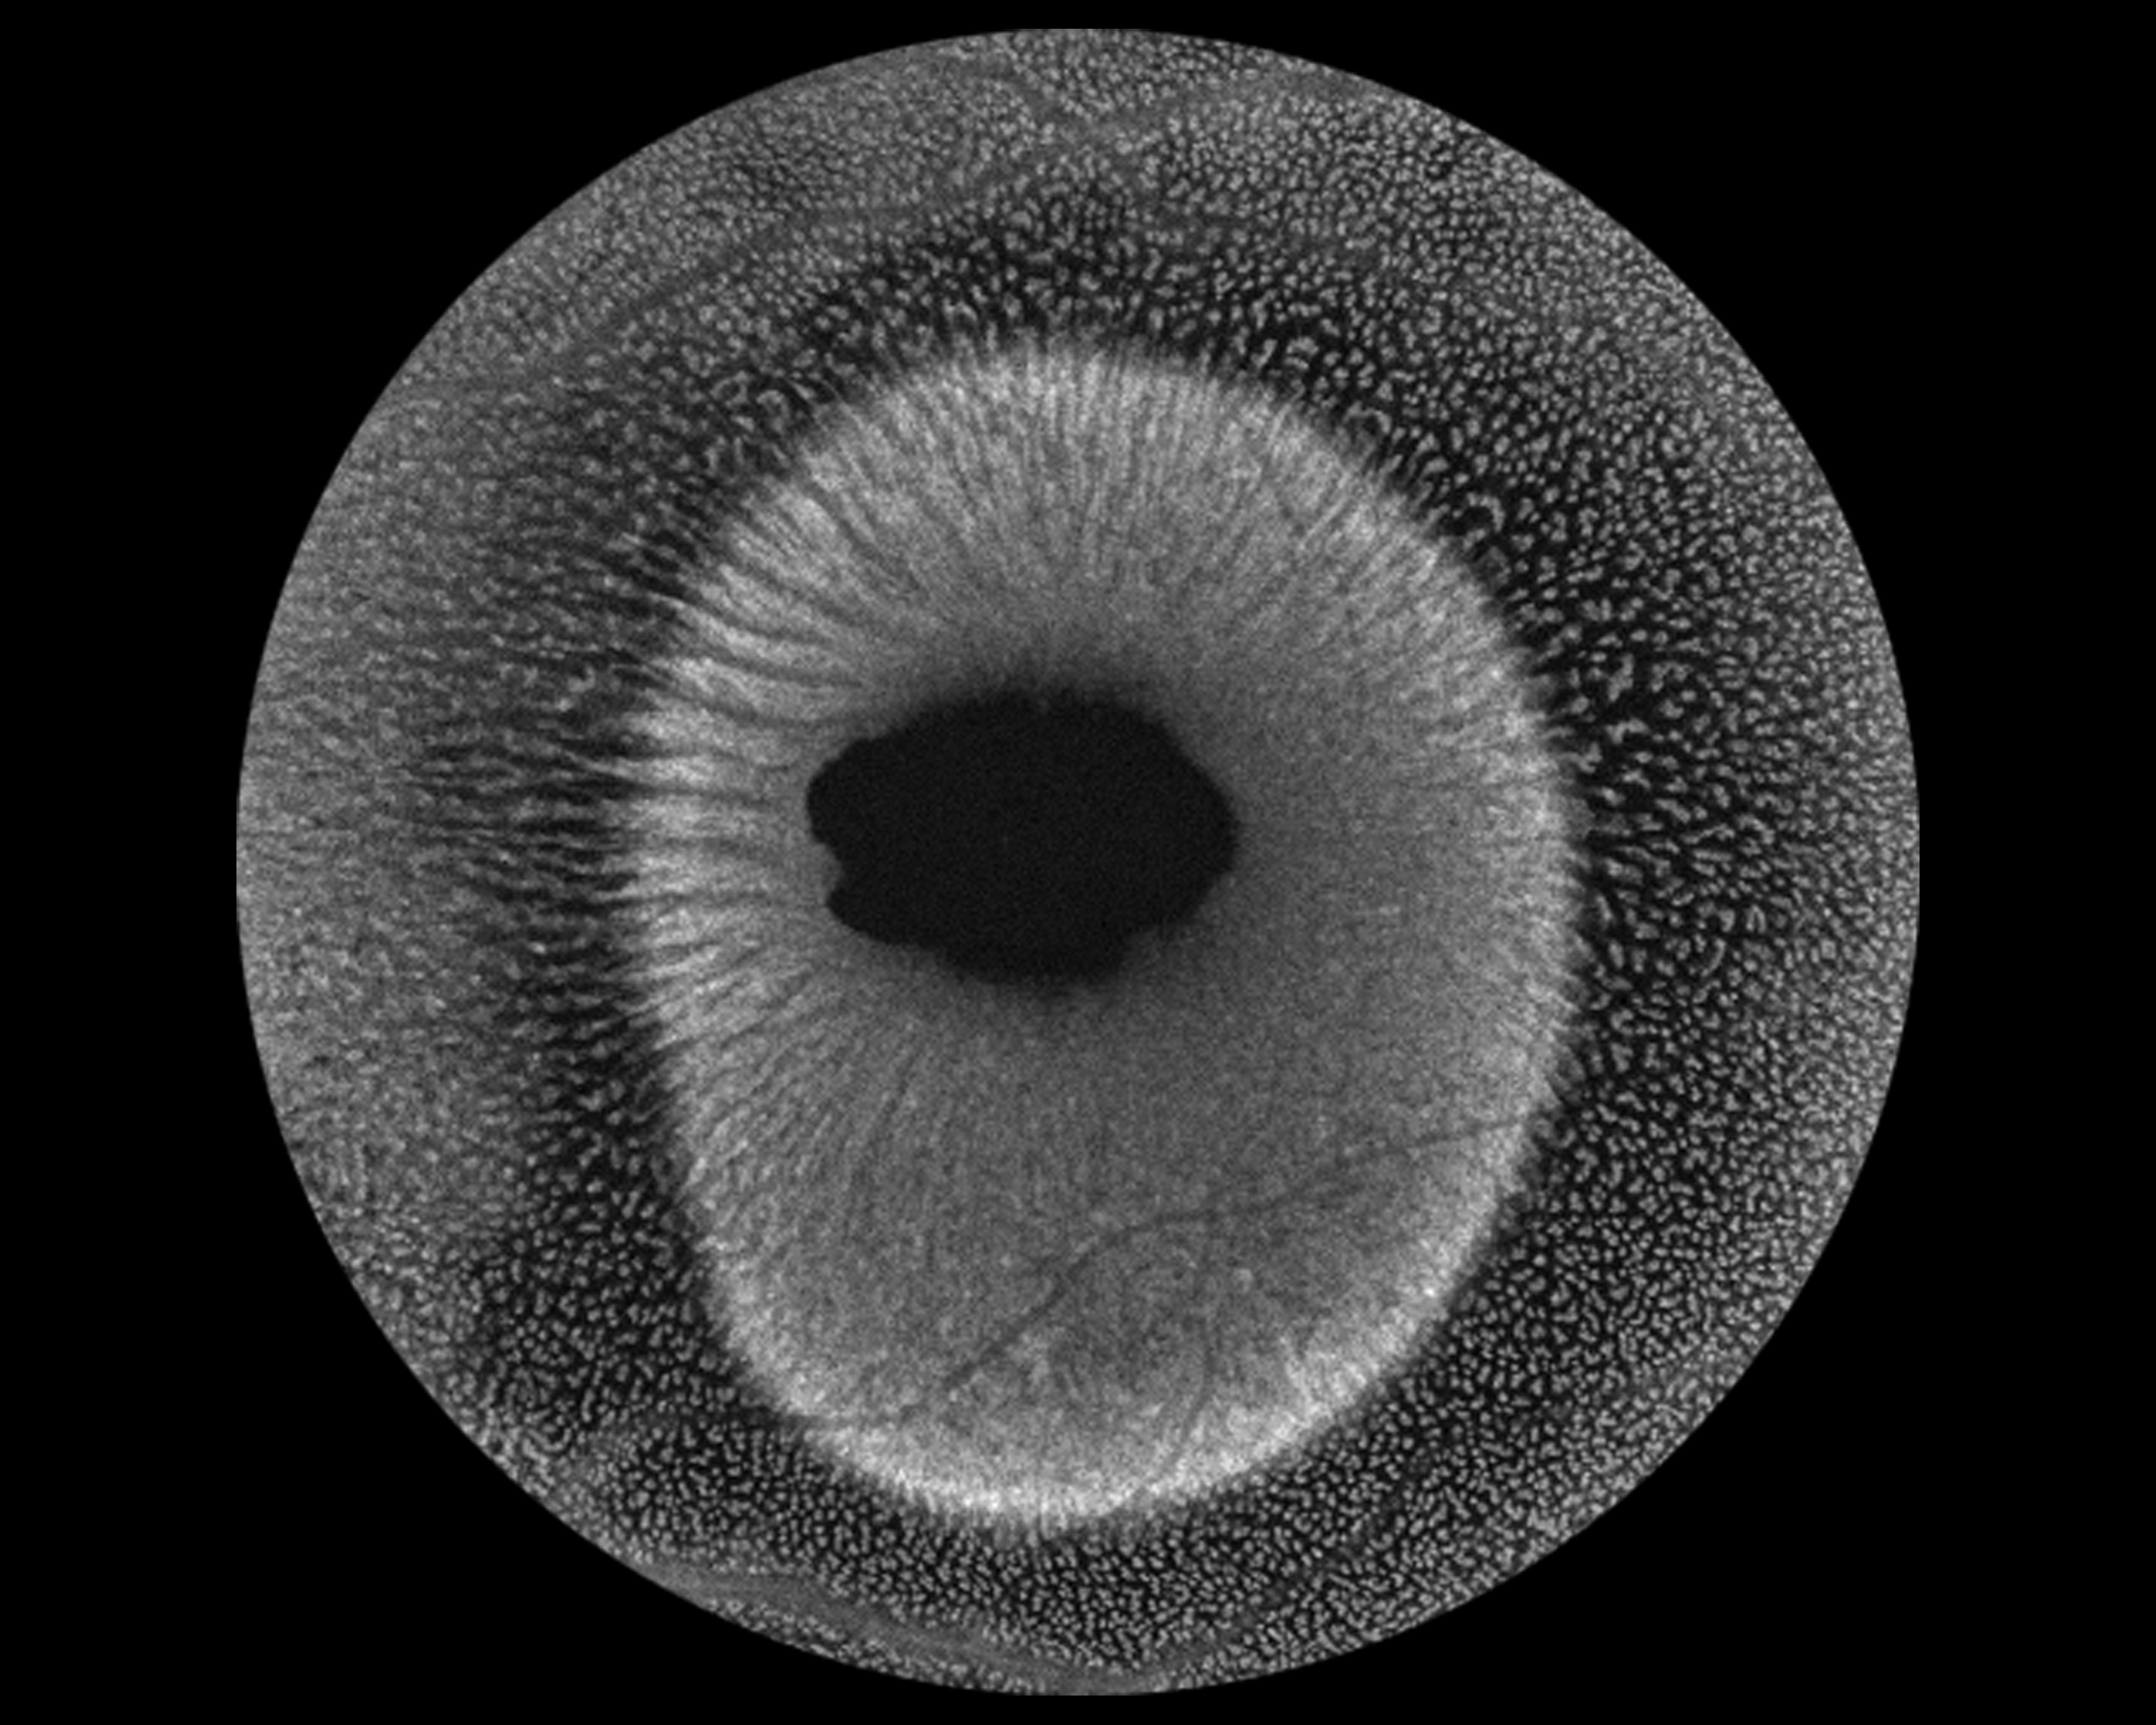

Macular Schisis Presented by Virginia Gebhart This photograph received First Place, Monochromatic in the 2025 OPS Scientific Exhibit. Filed Under Retina OPS Photo